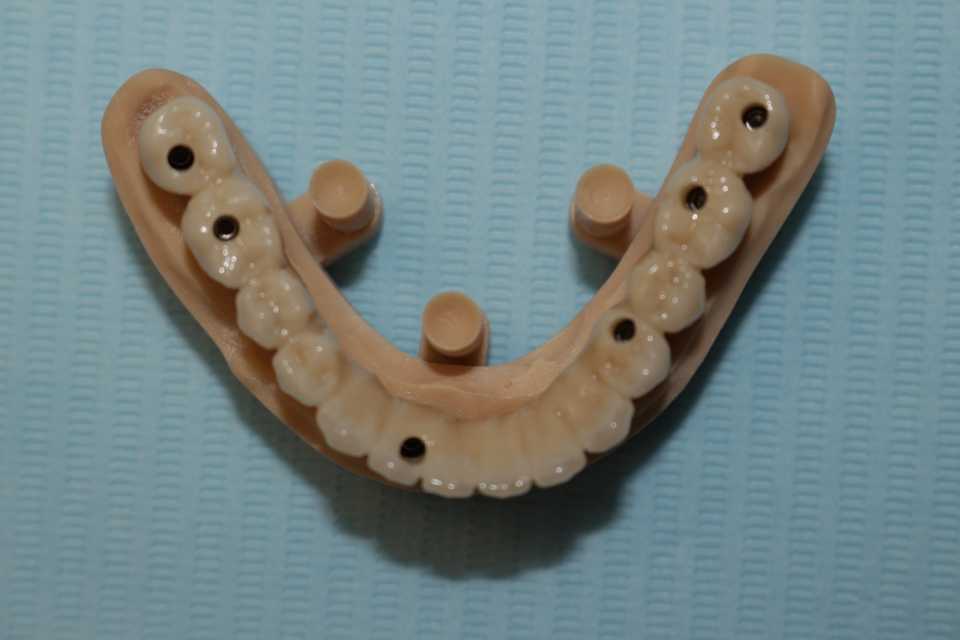

Împreună cu pacientul am hotărât realizarea unei lucrări protetice fixe inșurubabile pe 6 implanturi (implanturi Paltop). Lucrarea a fost realizată din ceramică pe zirconiu.

Implantul Paltop oferă posibilitatea realizării unor lucrări cu o estetică impecabilă și o afectare minimă a țesuturilor la locul implantării. Profilul concav al bontului protetic ajută la formarea unui țesut gingival dens la nivelul legăturii transgingivale scăzând vizibilitatea bontului.